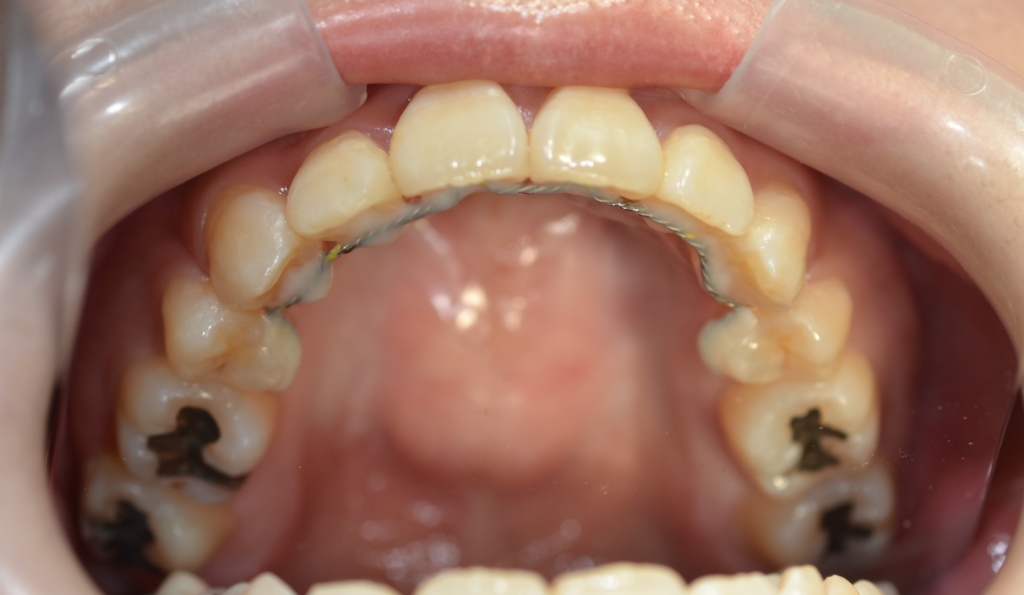

【上の歯列の更なる後方へ移動を図る】

あらためて、上顎にアンカースクリューを植立することにしました。

アンカースクリューを用いて矯正力を加えることで、上顎歯列全体を後方へ移動させて、口元の見た目の更なる改善を図ります。

【保定】 上下ともフィックスタイプ&クリアリテーナー

【治療装置】 スタンダードtypeのマルチブラケットシステム、

アンカースクリューを2本

PLAS & パラタルバー